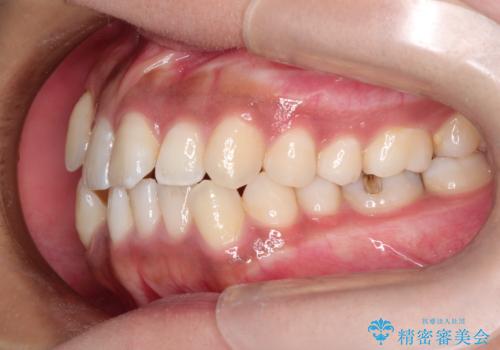

インビザラインと補助装置の併用による八重歯の抜歯矯正

- 八重歯を治したいとのことで来院されました。

重なりが強い右側の上下の歯を1本ずつ抜歯する計画としました。

インビザラインでの治療がご希望でしたが、右上の歯のかさなりが強いところは、補助装置である程度動かしてからインビザラインに移行することにしました。

下顎はインビザラインのみで治療を行いました。

インビザラインだけで歯を動かすよりも、補助装置を併用することにより効率的に、短期間で治療を行うことができる場合があります。